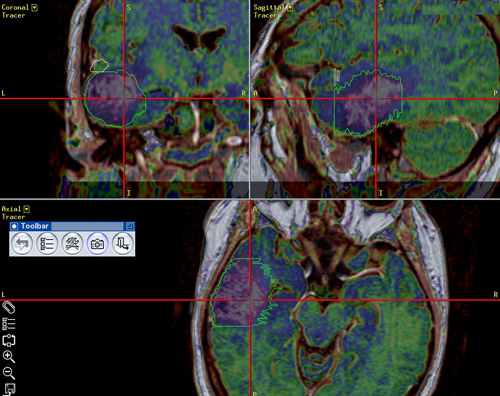

Ενδείξεις Η κύρια χρήση της νευροπλοήγησης είναι στη χειρουργική των χωροκατακτητικών εξεργασιών του εγκεφάλου, όπως οι όγκοι και τα ενδοεγκεφαλικά αποστήματα. Μπορεί επίσης να χρησιμοποιηθεί για την λήψη βιοψιών με στερεοτακτική μέθοδο, χωρίς όμως να χρειάζεται να τοποθετηθεί στερεοτακτικό πλαίσιο στην κεφαλή του ασθενούς. Περιγραφή Η μέθοδος συνίσταται στην δημιουργία μιας τρισδιάστατης ανασύνθεσης με ψηφιακό τρόπο ενός μοντέλου του εγκεφάλου του ασθενούς (με βάση τις πληροφορίες που λαμβάνονται από μια μαγνητική, ή σπάνια αξονική, τομογραφία του εγκεφάλου που πραγματοποιείται με ειδικό πρωτόκολλο), και στην χρήση αυτού του μοντέλου στο χειρουργείο για την ακριβή εύρεση της θέσης της χωροκατακτητικής εξεργασίας. Η ανασύνθεση των εικόνων γίνεται με την βοήθεια υπολογιστή και ειδικού εξοπλισμού και το ίδιο ισχύει για την ταύτιση του μοντέλου με την πραγματική θέση της κεφαλής στο χειρουργείο. |

Στο μοντέλο αυτό μπορούν να συνεισαχθούν και πληροφορίες από άλλες ακολουθίες της μαγνητικής τομογραφίας, π.χ. λειτουργικές ακολουθίες όπου απεικονίζονται θέσεις κέντρων του λόγου ή της κίνησης ή ακολουθίες δεσμιδογραφίας όπου απεικονίζονται νευρικές οδοί στο βάθος του εγκεφάλου. Ο χειρουργός έχει έτσι την δυνατότητα να σχεδιάσει προεγχειρητικά την επέμβαση, αποφεύγοντας για παράδειγμα προσπελάσεις που αυξάνουν τον κίνδυνο τραυματισμού ευγενών περιοχών του εγκεφάλου ή μεγάλων αγγείων. Η ταύτιση του ψηφιακού μοντέλου με τον προεγχειρητικό σχεδιασμό και της πραγματικής ανατομίας γίνεται στο χειρουργείο με την |

Δεσμιδογραφία (DT MRI) εγκεφάλου |

βοήθεια ειδικού εξοπλισμού και το τελικό αποτέλεσμα προβάλλεται στην οθόνη του νευροπλοηγού και στο χειρουργικό μικροσκόπιο καθ' όλη τη διάρκεια της χειρουργικής παρέμβασης.